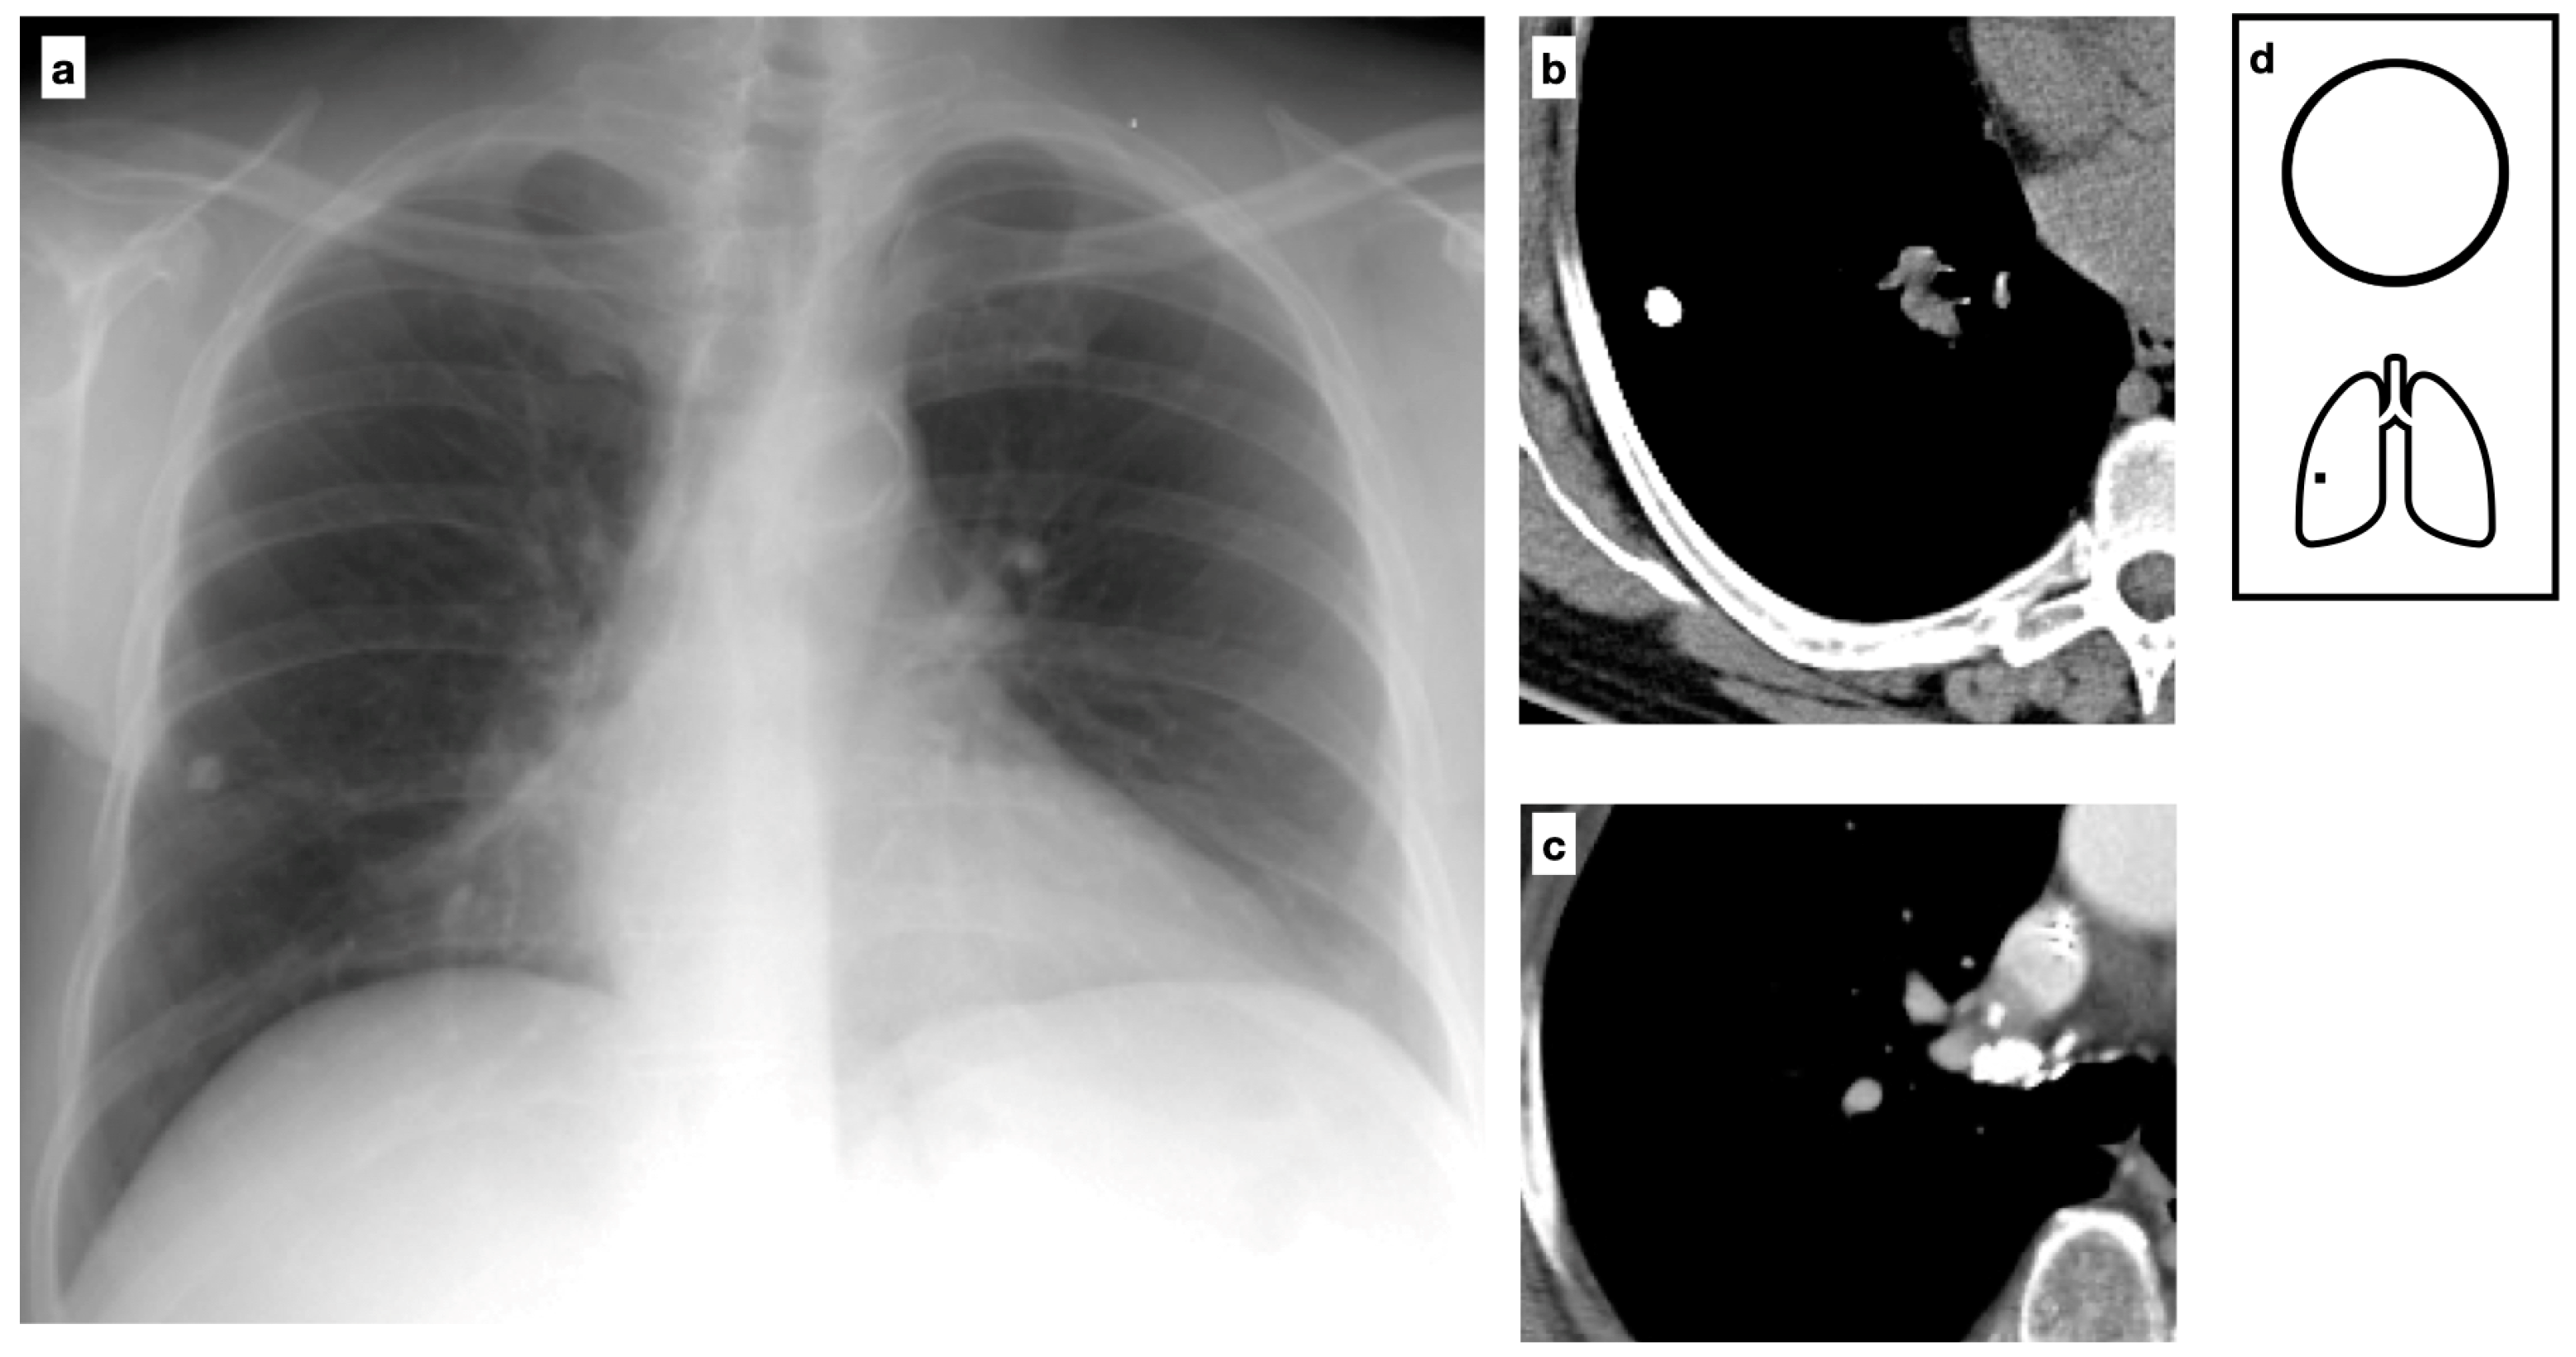

Figure 3.

Chest X-ray shows a uniformly calcified lung nodule in the peripheral region of the right lower lobe (a). CT confirms the presence of a nodule with diffuse calcification, consistent with a Ghon focus, associated with ipsilateral calcific lymph nodes, forming the Ranke complex. The Ghon focus represents a site of primary tuberculosis with a fibrotic scar that may eventually calcify (b,c). Pattern of calcification (d).

Figure 4.

Chest X-ray shows a calcified lung nodule in the central region upper right lobe (a). Coronal HRCT multiplanar reconstruction confirms the presence of a well-defined nodule characterized by lamellate calcification and a necrotic center consistent with tuberculoma. One of the most severe manifestations of Mycobacterium tuberculosis (MTB) infection, tuberculoma often presents as a well-defined nodule with a caseous necrotic core, most commonly affecting the lungs and central nervous system (b). Satellite nodules are present in up to 80% of cases. Pattern of calcification (c).